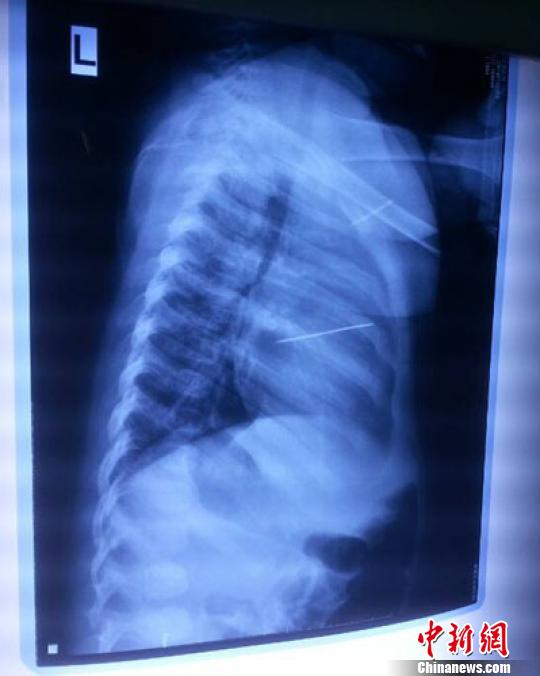

女嬰胸片提示心臟里面扎了一個縫衣針 蔡迅翔 攝

醫(yī)院胸心外科主任翟波介紹說,1月22日,小患者彤彤因為發(fā)燒抽搐來醫(yī)院就診,常規(guī)檢查時發(fā)現(xiàn)孩子心臟里面扎了一個縫衣針。

“第二天上午,我們做了個緊急彩超檢查,發(fā)現(xiàn)針是從患者右心室表面刺入,穿破室間隔,到達(dá)左心房,中間還有一部分損害到二尖瓣。于23號下午,我們就做了一個緊急手術(shù),手術(shù)中發(fā)現(xiàn),這枚針已經(jīng)刺入心臟,沒入了右心室的下面,表面已經(jīng)看不到針了,僅能看到一個小針眼,還在往外滲血,一點一點的滲,心包腔里面大概有100多毫升的出血,心包上一個洞,針在右心室表面刺入以后,穿過室間隔,在二尖瓣的上方,進(jìn)入了左心房,在針的四周,有很多纖維沉積物,包繞著這枚針。”翟波說,他們把針取出來以后,測量了一下,長度大概是五厘米,同時發(fā)現(xiàn)這個針給患者左心房的后壁造成了一定的損傷,左心房的后壁已經(jīng)損傷了三分之二,還剩下有左心房的外膜,很薄的一層,如果這一層再破的話,這個孩子將會引起大出血,很快就會死亡。